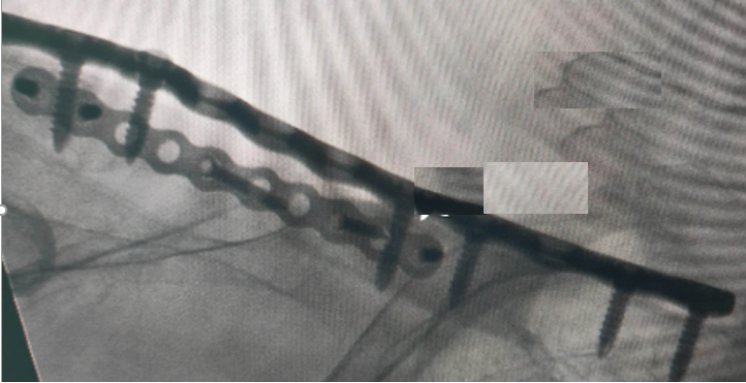

或是粉碎性骨折区域,螺钉固定过多或是捆扎钢丝等使得应力过于集中,也会造成钢板断裂。如下图。

通过生物力学实验发现,钢板跨度不足和螺钉固定不充分是导致钢板断裂的主要力学因素。